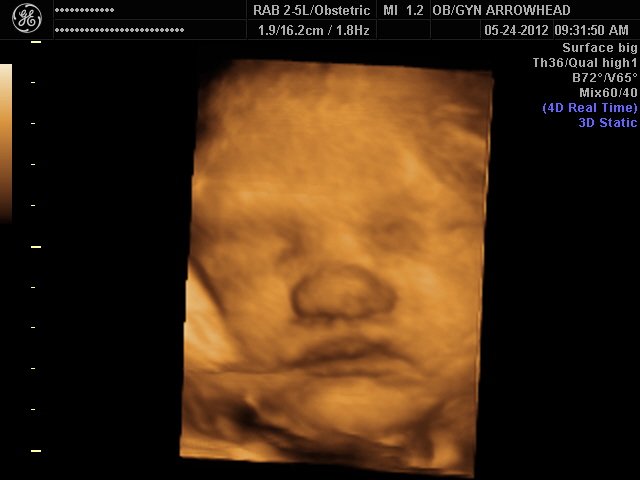

We offer complimentary 3D/4D Ultrasounds to all our OB patients around 30 weeks! The following photos are some examples of our work, shown with permission from our patients.